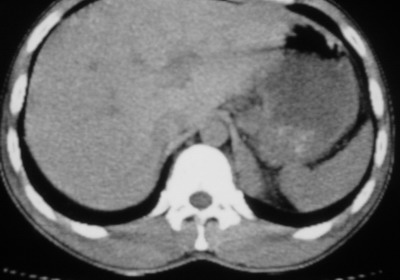

以下是引用余辉在2007-6-16 20:47:00的发言:[br]图像不边续,1左肺下叶膈后囊性病灶,与胃有密切联系,考虑局限性膈膨隆,不排除其他如脓肿等;2左膈肌脚增厚,其前方肝胃间隙内可见球形病灶,左肾上腺病变?进一步检查

以下是引用xulianj在2007-6-16 21:14:00的发言:[br]左膈肌脚增厚,支持膈肌角病变。

以下是引用卜一在2007-6-17 4:50:00的发言:[br]左膈肌脚增厚,支持膈肌角病变。